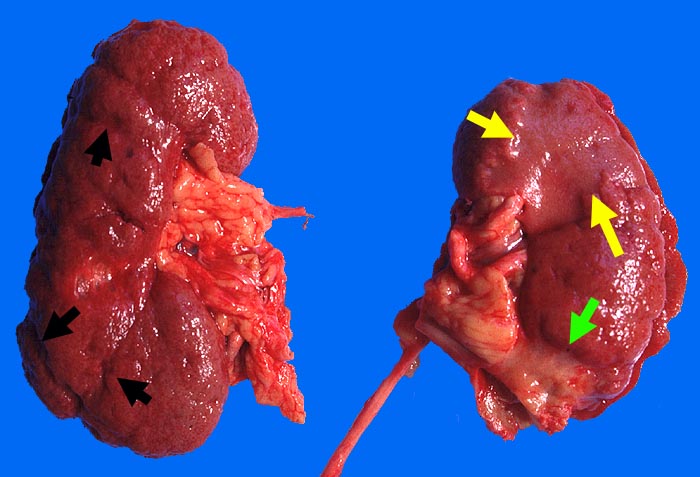

Je nach Grösse des verschlossenen Gefässes sind unterschiedlich grosse (wenige Millimeter bis mehrere Zentimeter) solitäre oder multiple scharf begrenzte Herde erkennbar. Nach etwa einer Woche imponiert der akute Infarkt als gelber erhabener Bezirk mit 2-5mm breitem rotem Randsaum. Subakute Infarkte bilden flache homogene rote Herde. Nach Monaten bildet sich eine scharf begrenzte weisse Narbe aus. Infolge unterschiedlicher Kollateralversorgung z.B. via Arteria spermatica oder ovarica führt der Verschluss der Arteria renalis nicht immer zur Totalnekrose. Das Endstadium grosser Infarkte bildet die grob gebuckelte Infarkt-Schrumpfniere.